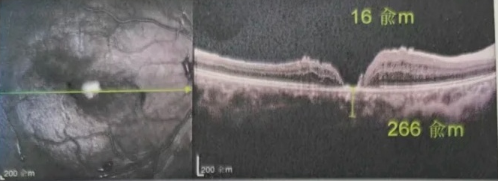

最讓吳爺爺難以置信的是:術(shù)后只需保持平躺24小時!第二天復(fù)查時,眼底鏡及OCT檢查清晰顯示——那個折磨了他大半年的大裂孔,竟然閉合了!且吳爺爺?shù)挠已垡暳τ辛嗣黠@的改善,術(shù)后3天已經(jīng)可以看到 0.15。